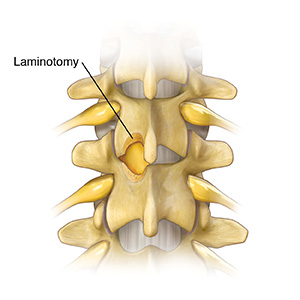

Removing bone

During a microdecompression, bone is taken out. First, a small part of the lamina is removed. It is taken from the vertebrae above and below the pinched nerve. Removing part of the lamina is called a laminotomy. Taking out all the lamina is called a laminectomy. If there is no disk problem, the small opening made by this process may take pressure off the nerve. But most often, more bone, ligaments, or both are pressing on a nerve. This bone and the ligaments are also taken out.

| Part of the lamina is removed from the vertebrae above and below the pinched nerve. |